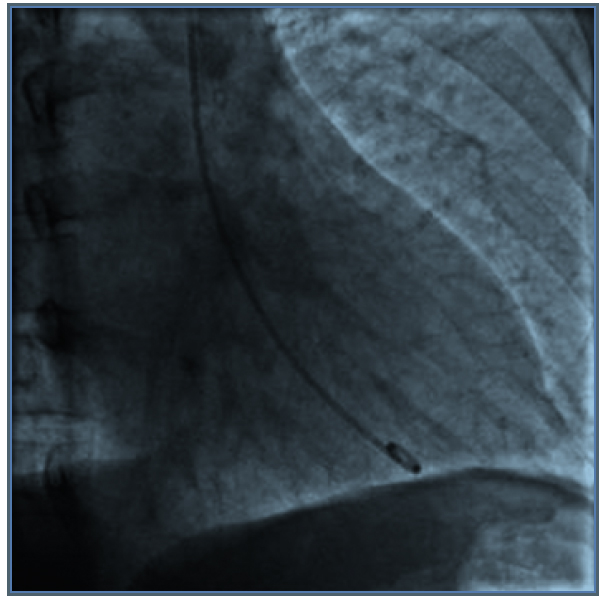

Consultó en urgencia por cuadro de dolor retroesternal de inicio agudo, opresivo, irradiado a dorso, diaforesis y palpitaciones. A su ingreso destaca: presión arterial (PA) 214/120 mmHg, frecuencia cardiaca (FC) 126 x min, mala perfusión, somnolencia y manchas café con leche. Las enzimas cardiacas mostraron valores normales. El ECG reveló supradesnivel de ST y T negativas de V2 a V4, con Q patológica en V5-V6-DI y AVL. Coronariografía: Coronarias sin lesiones, hipokinesia difusa con fracción de eyección (FE) de 20%. Interpretándose como miocardiopatía de Takotsubo (MTT) (Figura 1). En base a los hallazgos con alta sospecha de feocromocitoma, se solicita metanefrinas urinarias totales: 6,3 mg/24 h (VN: 0-1), TSH 2,32 uIU/ml PTH: 46,1 pg/ml Ca 9,5 mg/ dl, P: 4 mg/dl, Alb: 4,3g/dl Calcitonina basal: 4,8 pg/ml (VN: < 4). Ecografía renal descartó estenosis de arterias renales con masa renal sugerente de neoplasia. TC con contraste: masa suprarrenal derecha de 6,3 cm de eje mayor con características de feocromocitoma (Figura 2).

Figura 2. A: fase arterial; B: fase.